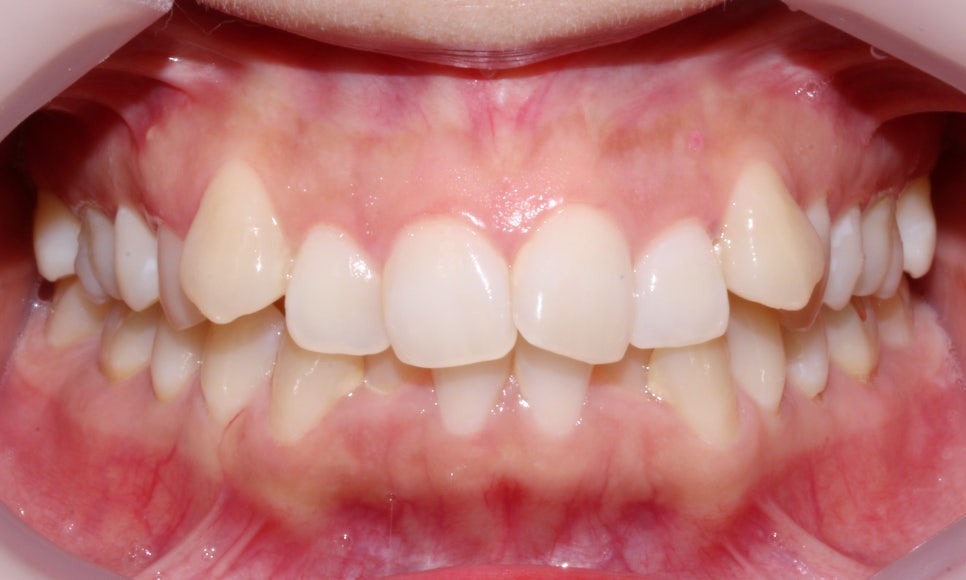

돌출입, 덧니교정 2D교정으로 진행 (전 사진)

돌출입, 덧니치아 2D교정으로 완성! by.투디치과(2D치과)

교정 중 크게 티가 나지 않는 것을 원하셔서

치아 상태를 살피고 적당한 치료방법이 있는지

정밀 진단을 진행했습니다.

상악과 하악의 교합면이 고르지 못하고

덧니로 인해 치열에 총생이 생겨

심미적으로 좋지 못한 상태입니다.

하악의 경우 덧니로 인해 치아 사이의 공간이

매우 좁아 전치부의 치아가

삐뚤빼뚤해 보이기까지 합니다.